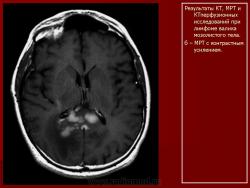

Лимфомы головного мозга.

1.Uv_.Slayd48.JPG2.Uv_.Slayd49.JPG3.Uv_.Slayd50.JPG4.Uv_.Slayd51.JPG5.Uv_.Slayd52.JPG6.Uv_.Slayd53.JPG7.Uv_.Slayd54.JPG8.Uv_.Slayd55.JPG9.Uv_.Slayd56.JPG10._Uv.Slayd57.JPG11.Uv_.Slayd58.JPG